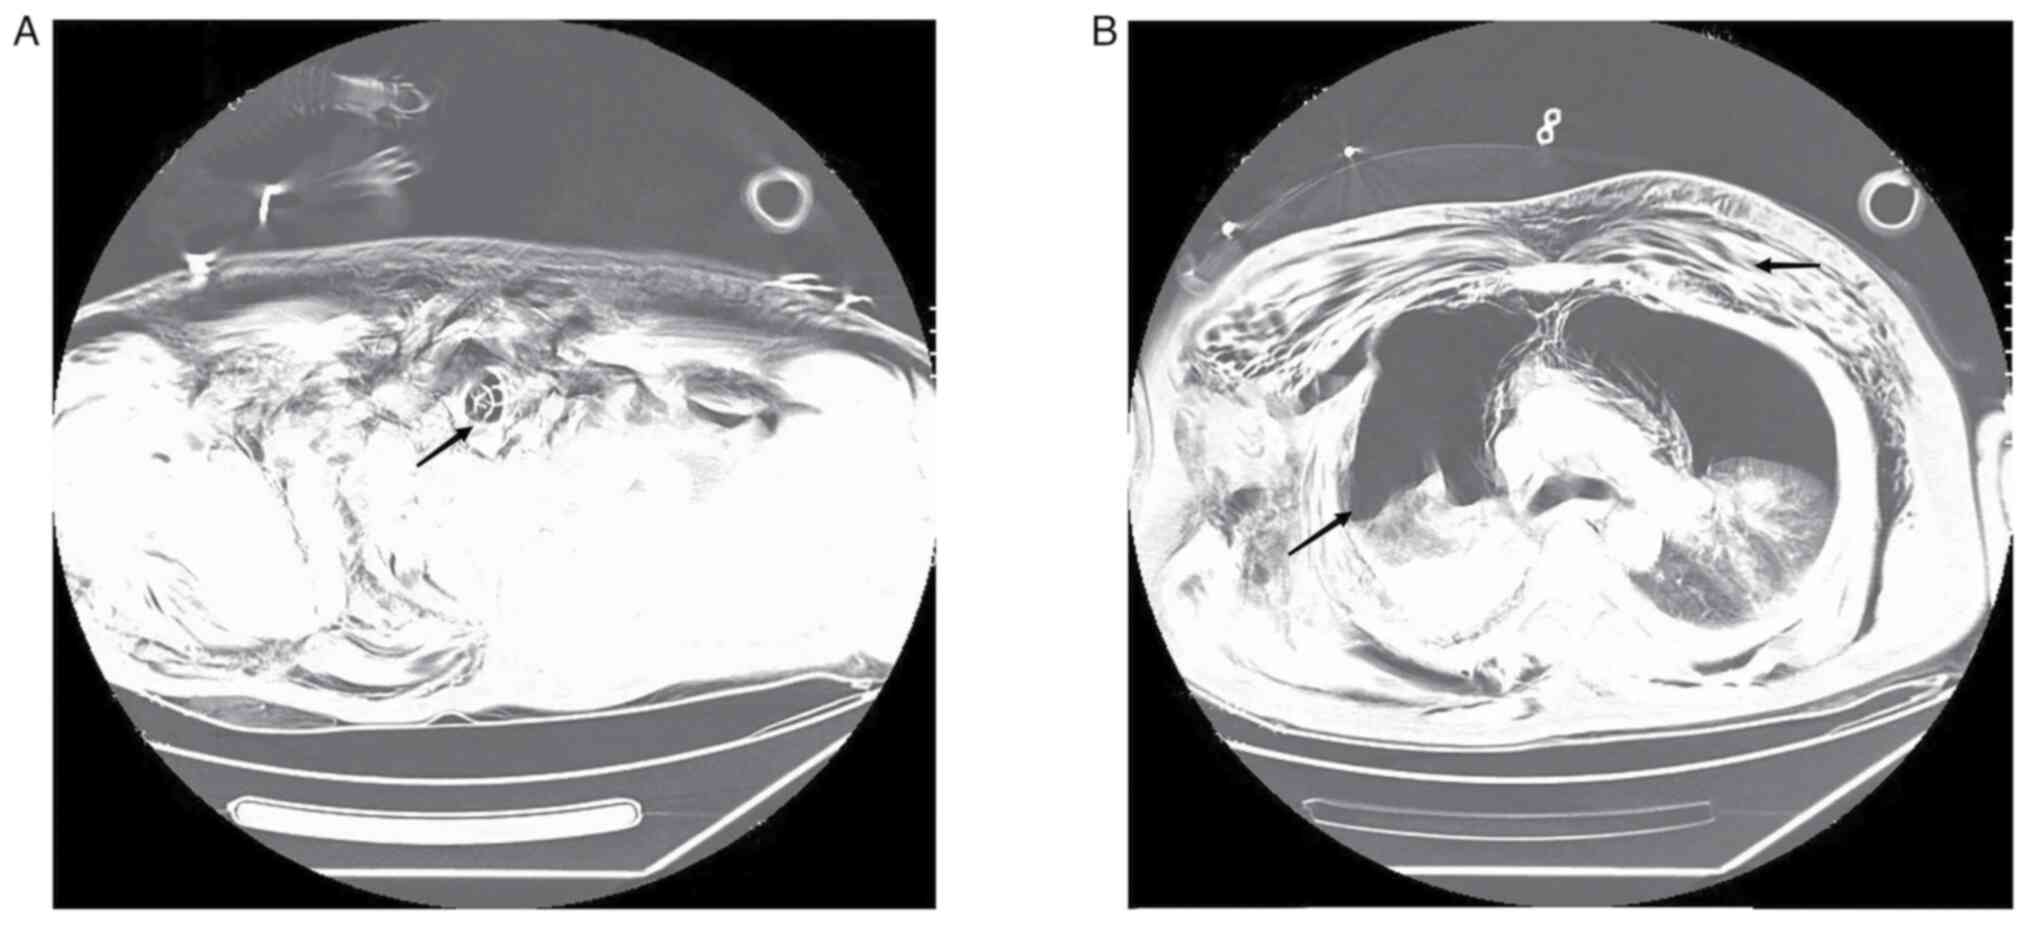

Figure 4

CT scan of the chest 10 days after injury (axial view). (A) The black arrow indicates the main bronchus did not collapse after tracheotomy. (B) The black arrow indicates lungs were not compressed, and the pneumothorax and subcutaneous emphysema had been absorbed.

After ECMO decannulation, ventilator therapy was used under volume control mode (tidal volume, 8 ml/kg; respiratory rate, 25 breaths/min; positive end-expiratory pressure, 5 mmHg; oxygen concentration, 50%). Following the withdrawal of the ECMO machine, a chest CT was performed. Bilateral lung effusion and pleural effusion were reduced, and pneumothorax and subcutaneous emphysema was partially absorbed in the chest wall compared with the patient's condition at the time of admission. At 7 days after the injury, the patient's consciousness was similar to that on arrival at the trauma center, which may be related to craniocerebral injury or cerebral anoxia due to ventricular escape rhythm, and expectoration was poor. When the tracheal catheter was used for sputum aspiration, only ~20 cm of the sputum aspiration tube could be inserted. A fiberoptic bronchoscopy was performed and when the fiberoptic tracheoscope probe was inserted into the tracheal repair site, it was found that the tracheal cartilage had collapsed, resulting in airway stenosis (Fig. 3). In consultation with the Department of Otolaryngology, Jiaxing First Hospital, a tracheotomy was recommended. A tracheal tube was placed under the inferior tracheal cartilage through a median cervical incision. The patient was treated with high-flow oxygen therapy after tracheotomy and was then transferred to a general ward for rehabilitation. On the 10th day after injury, chest CT indicated that lungs were not compressed, and the pneumothorax and subcutaneous emphysema had been absorbed (Fig. 4). After 24 days of hospitalization, the patient's consciousness had improved; however, they could not take care of themselves. The patient was transferred back to the hospital of the first presentation, Jiashan First People's Hospital (Jiaxing, China), for rehabilitation treatment. The patient was discharged after 58 days of rehabilitation. In January 2023, the patient is off the ventilator, but is unconscious, bedridden and unable to care for themselves.